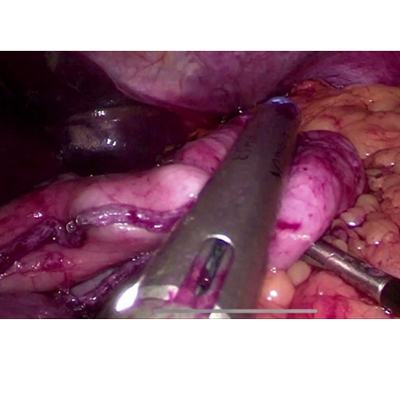

ADVANCE LAPAROSCOPIC SURGERY

SURGERY FOR CANCER OESOPHAGUS

LAPAROSCOPIC SURGERY FOR BILIARY CYST

LAPAROSCOPIC WHIPPLES PROCEDURE

We have state of the art operating theatre with advanced surgical equipments. We have a Karl Storz Spies advanced HD laparoscopy operating system in addition to a 3 chip laparoscopy. We have installed advanced vessel sealing devices like Gen 11 harmonic scalpel, Ligasure from Valley Lab & Argon plasma coagulator. There is a recent addition of Cavitron Ultrasonic Aspirator (CUSA) system into our surgical armamentarium. We have the most recent powered Echelon endo-stapling devices. In addition to all these we have a constant supply of various types of advanced stapling devices for GI surgeries. Our endoscopy machines are having high definition with FICE Technology. Last but not the least we have semi flexible Ureteroscopy for managing common bile duct stones.